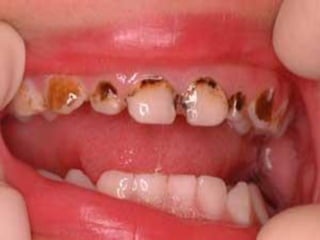

Menor de 3 años con

cualquier evidencia

de caries en

superficie lisa

Las primeras lesiones no son cavitadas

a medida que pasan los años

aparecen más lesiones cavitadas